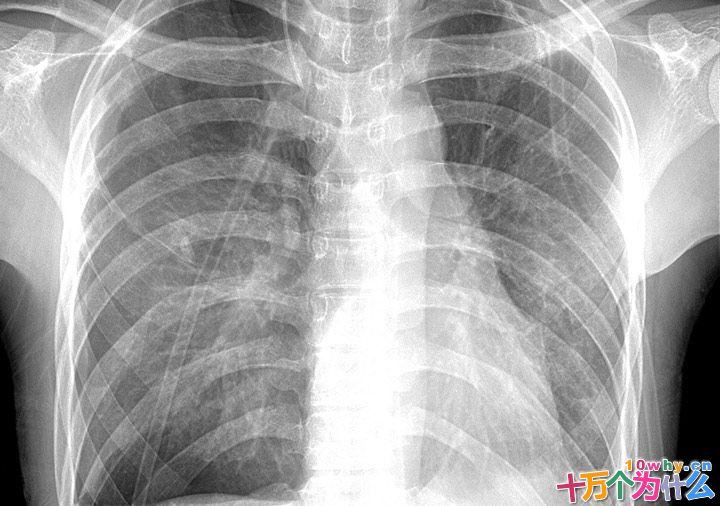

拍X线片时,得到最清晰影像的就是人体骨骼组织。含有钙盐的骨骼组织是密度最大的正常人体组织,其含有的钙元素可大量吸收X射线。与人体骨骼一样,各种金属也能大量吸收X射线,在感光底片上留下自己的影子。很多金属甚至能完全吸收X射线。如果在拍摄X线片时,患者身上有项链、硬币等金属做的东西,就会遮住医生想要看的人体结构,影响检查的效果。所以,拍X线片时,发卡、零钱、首饰等金属物品不能带在身上。